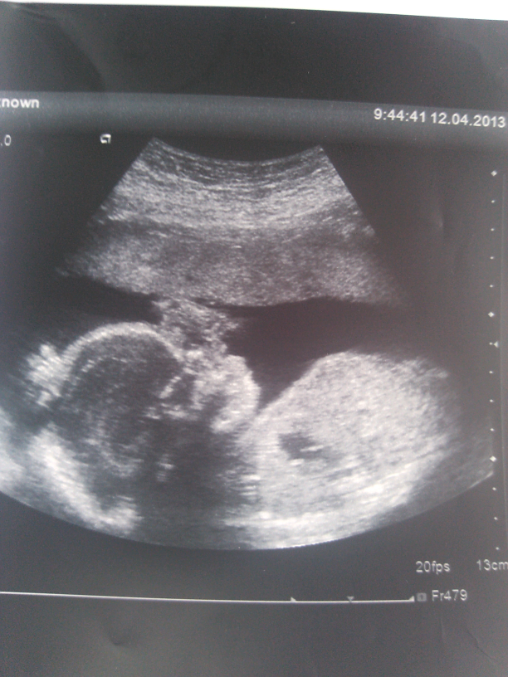

Вот моя крохотуля) "загорает" можно сказать) правую ручку м алышик закинул под голову, левой трогает ротик(как сказала врач "видимо пальчик сосет")

да ну а чего гадать) главное она сказала что все что нужно к этому сроку сформировалось, все на месте, печень, почки, сердечко, ручки, ножки. все соответствует сроку) и это ОТЛИЧНО)))

правда поставила частичное предлежание под вопросом, будем смотреть в эту пятницу, да и рановато меня Г отправила на УЗИ, сказала подрастите с недельку-досмотрим сердечко.